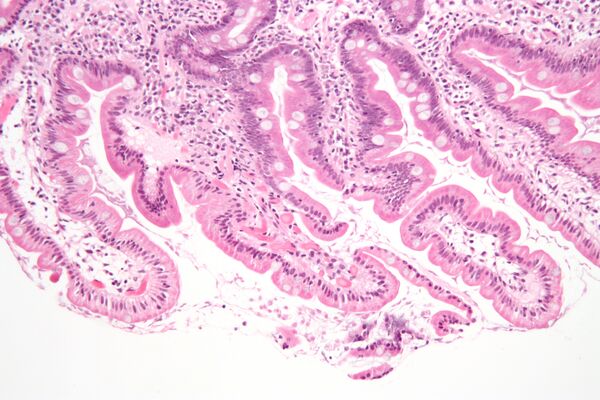

Гистология

Двенадцатиперстная кишка имеет особое гистологическое строение слизистой, делающее её эпителий более устойчивым к агрессивности как желудочной кислоты и пепсина, так и концентрированной жёлчи и панкреатических ферментов, чем эпителий дистальных отделов тонкой кишки. Строение эпителия двенадцатиперстной кишки отличается также и от строения эпителия желудка.

- В подслизистой основе двенадцатиперстной кишки (особенно в верхней её половине) располагаются дуоденальные (Бруннеровы) железы, по строению сходные с пилорическими железами желудка.